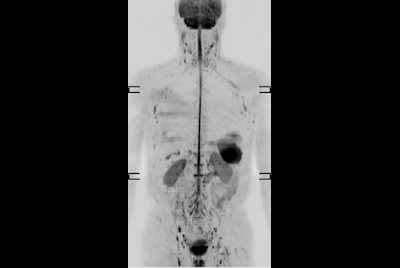

Advanced Body imaging - DWIBS